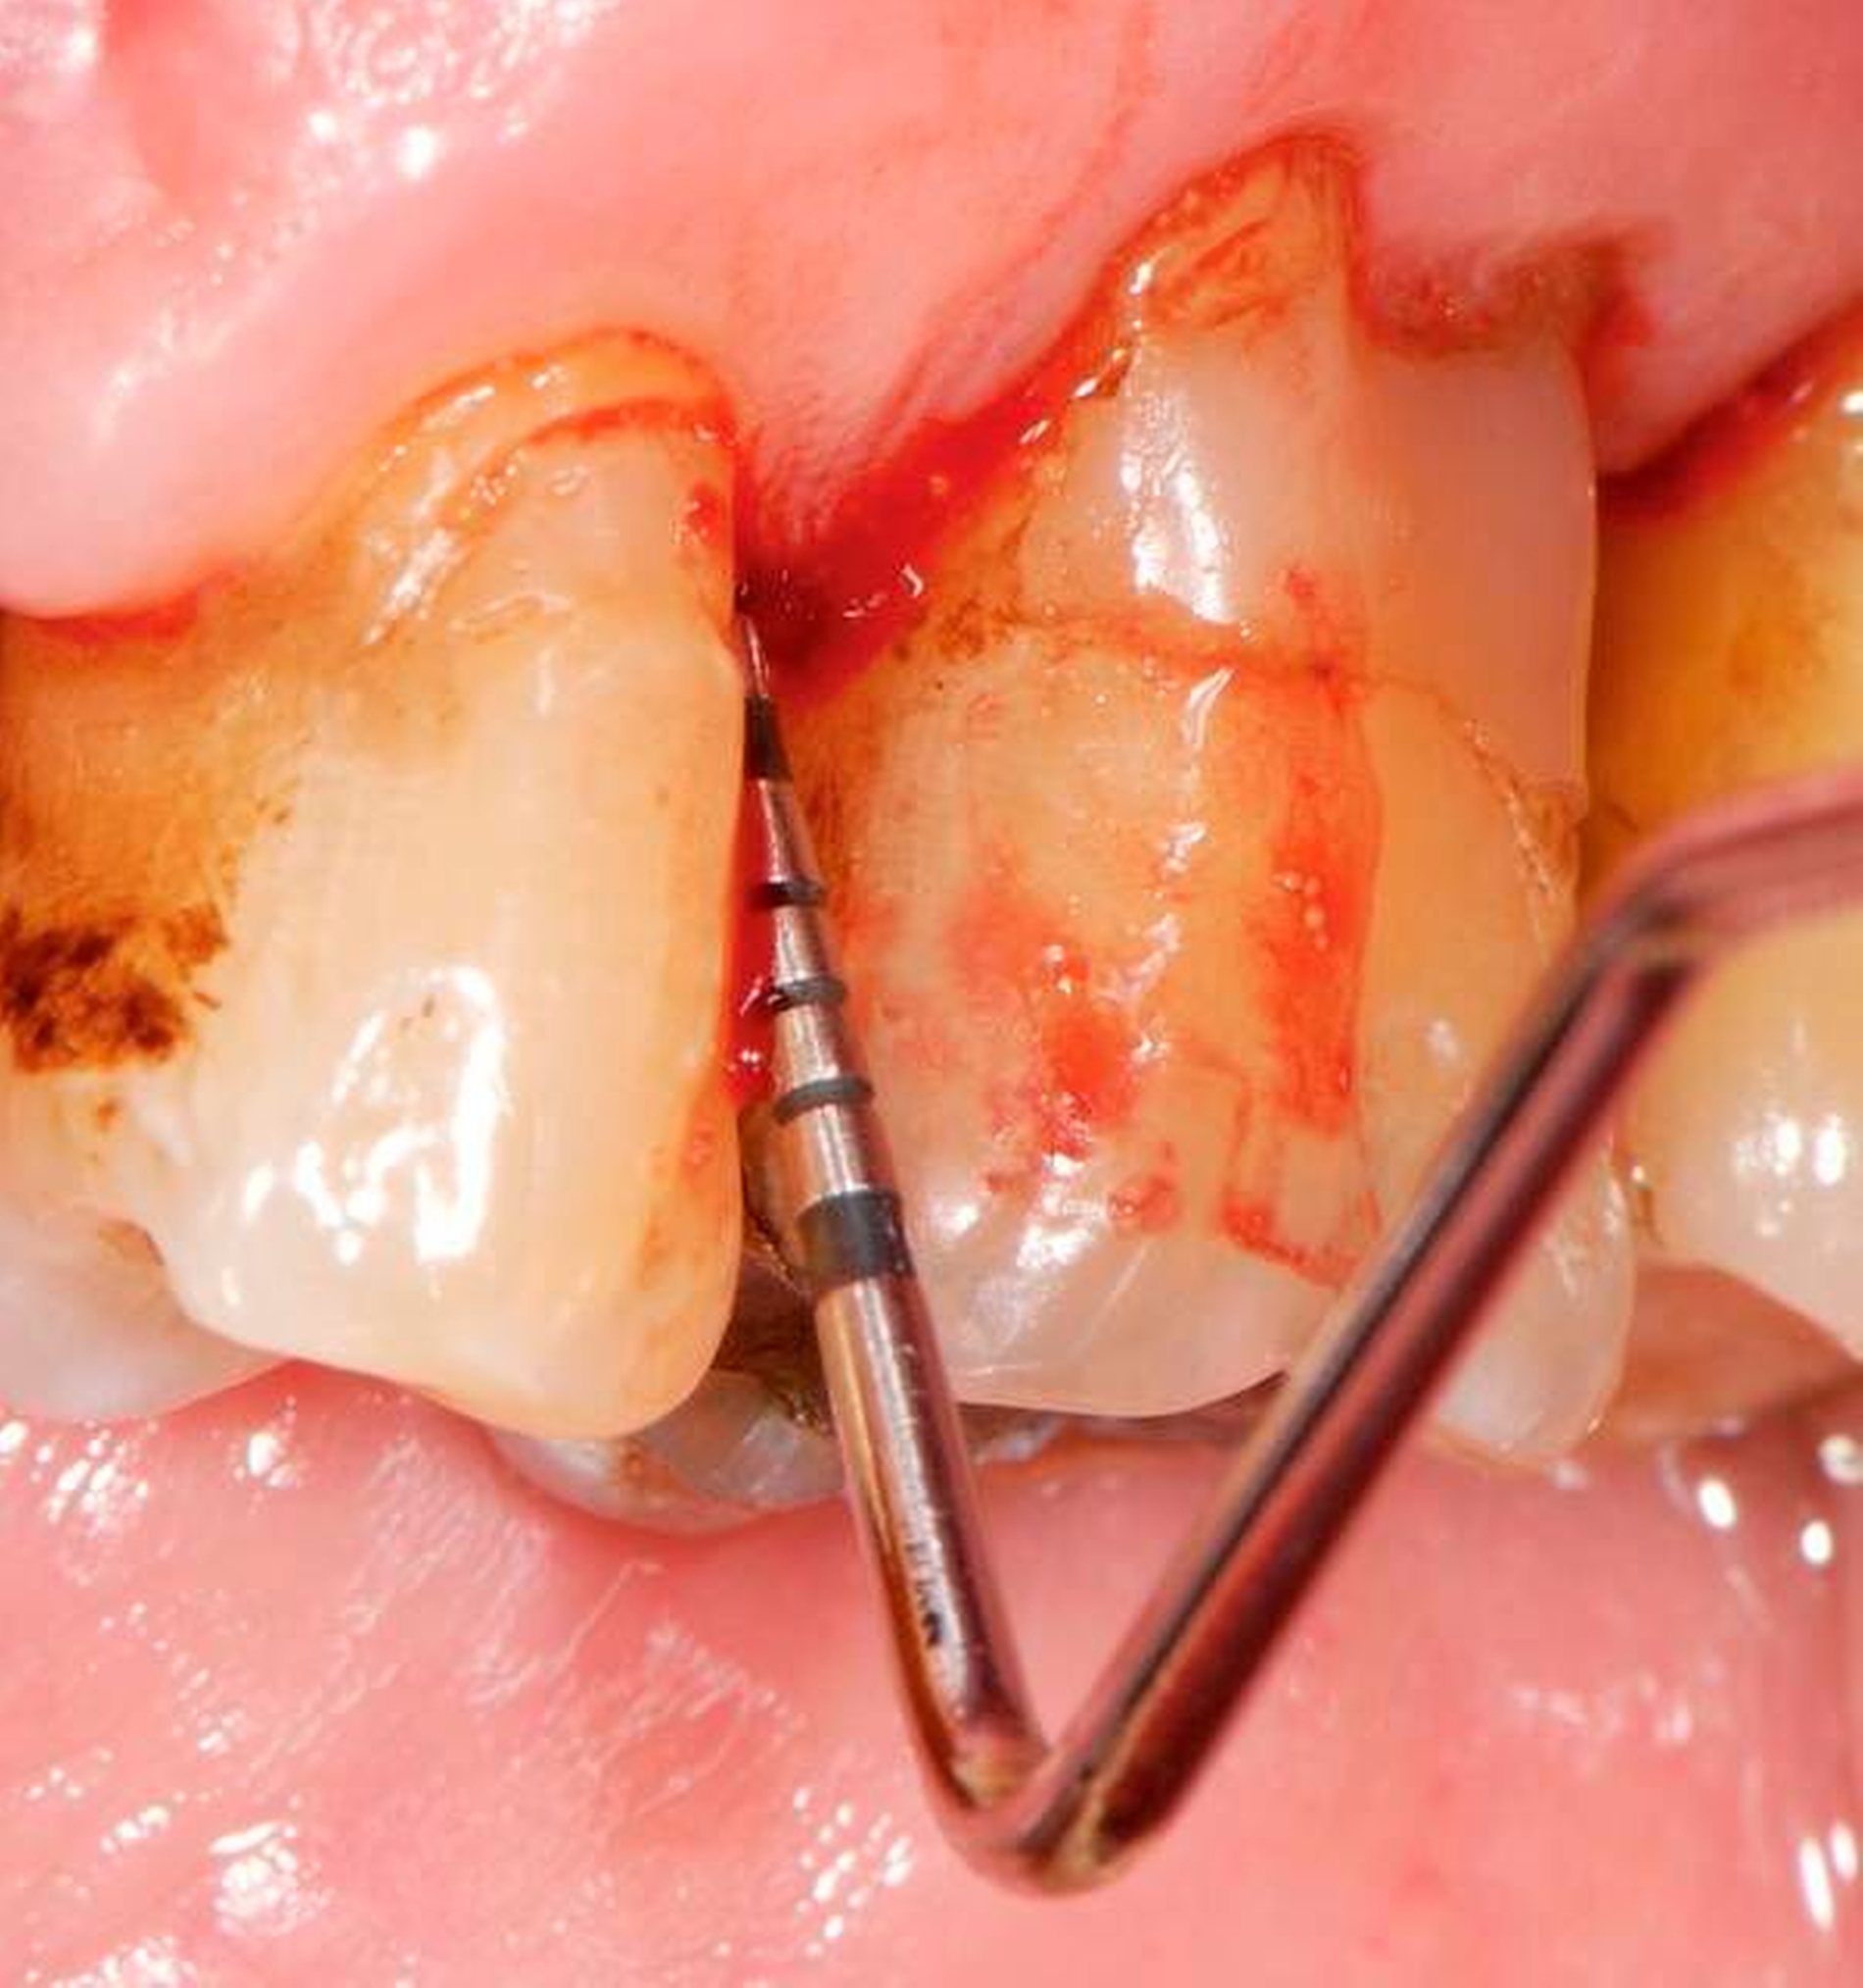

Abbildung 2: Direkte Teilüberkronung im Seitenzahnbereich (R1-Technik)

In den Abbildungen 1 bis 3 werden Optionen für frugale Interventionen auf restaurativem Sektor aufgeführt. Es handelt sich um direkte Vollüberkronungen im Frontzahnbereich (hier: hergestellt in R1-Technik / einphasig) (Abbildung 1), direkte Teilüberkronungen im Seitenzahnbereich (hier: hergestellt in R1-Technik / einphasig) (Abbildung 2), Reparatur-Restaurationen im Seitenzahnbereich (hier: hergestellt in R2-Technik / zweiphasig) (Abbildung 3). Technische Einzelheiten zur Vorgehensweise und den Ergebnissen sind an anderer Stelle beschrieben (Literatur siehe oben).

Für die in Abbildung 2 dargestellte Situation eines tief zerstörten Prämolaren gelten ähnliche Charakteristika. Es gibt in der restaurativen Zahnheilkunde viele Neuerungen, die das Behandlungsspektrum vergrößert haben. Dazu zählen unter anderem:

ein- oder zweiphasiges Vorgehen je nach Defektausdehnungen (R1- und R2-Technik),

von Präparationsgrenzen unabhängige Verschalungstechniken, die auch bei nicht-kariesbedingten Zahnhartsubstanzschäden (wie etwa Hypomineralisationen) zum Einsatz kommen können,

schadensgerechte Reparaturtechniken (Abbildung 3),

neuartige Insertionstechniken, die unter anderem die Anpassung neuer Restaurationen an vorhandene prothetische Versorgungen (Reziproktechnik) erlauben.